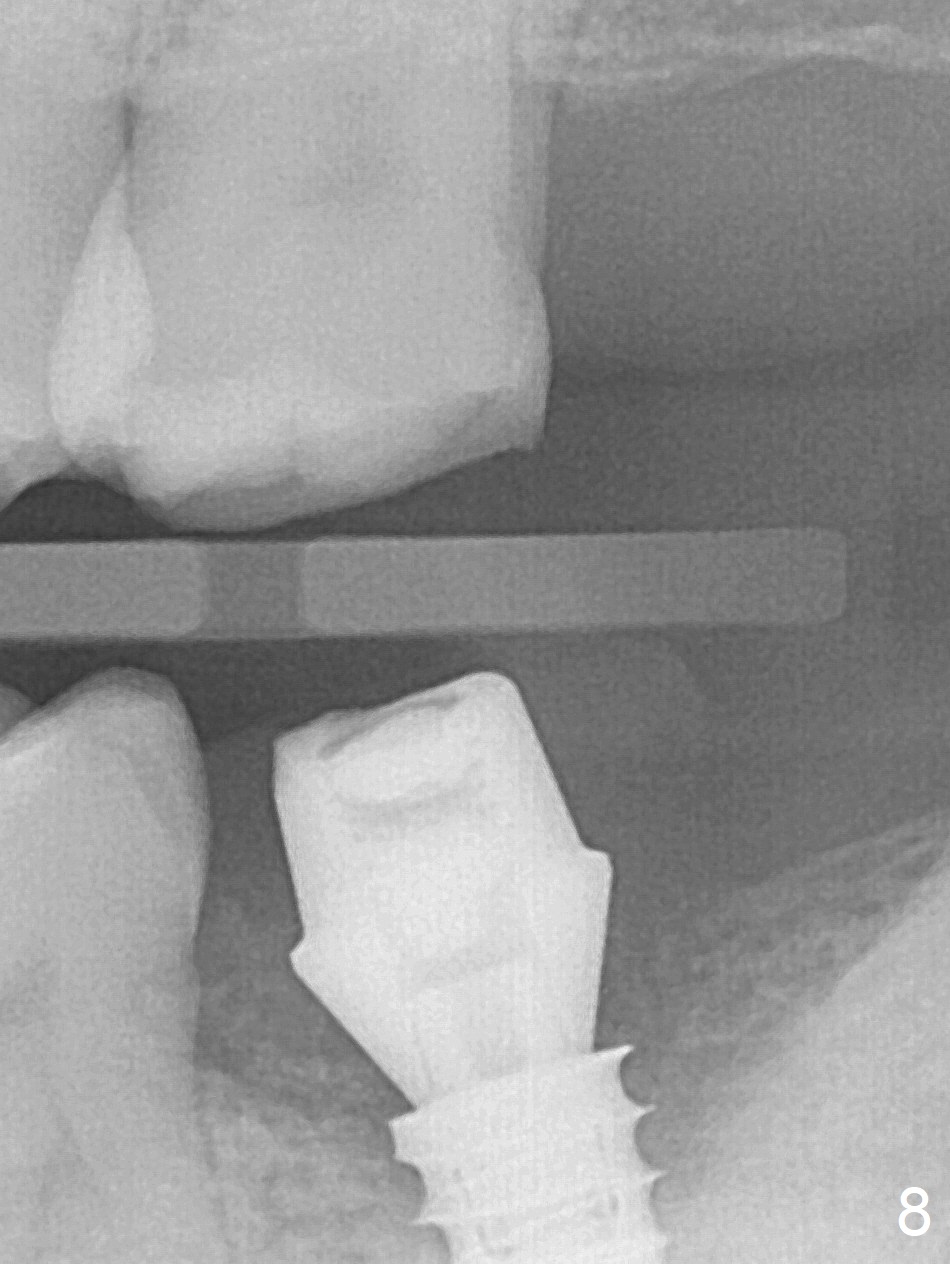

Three months postop, there is no bone resorption, while the bone graft seemingly remains in place (Fig.8).  Bony trabecule has grown into the distal socket 6 months post cementation (10 months postop, Fig.10).